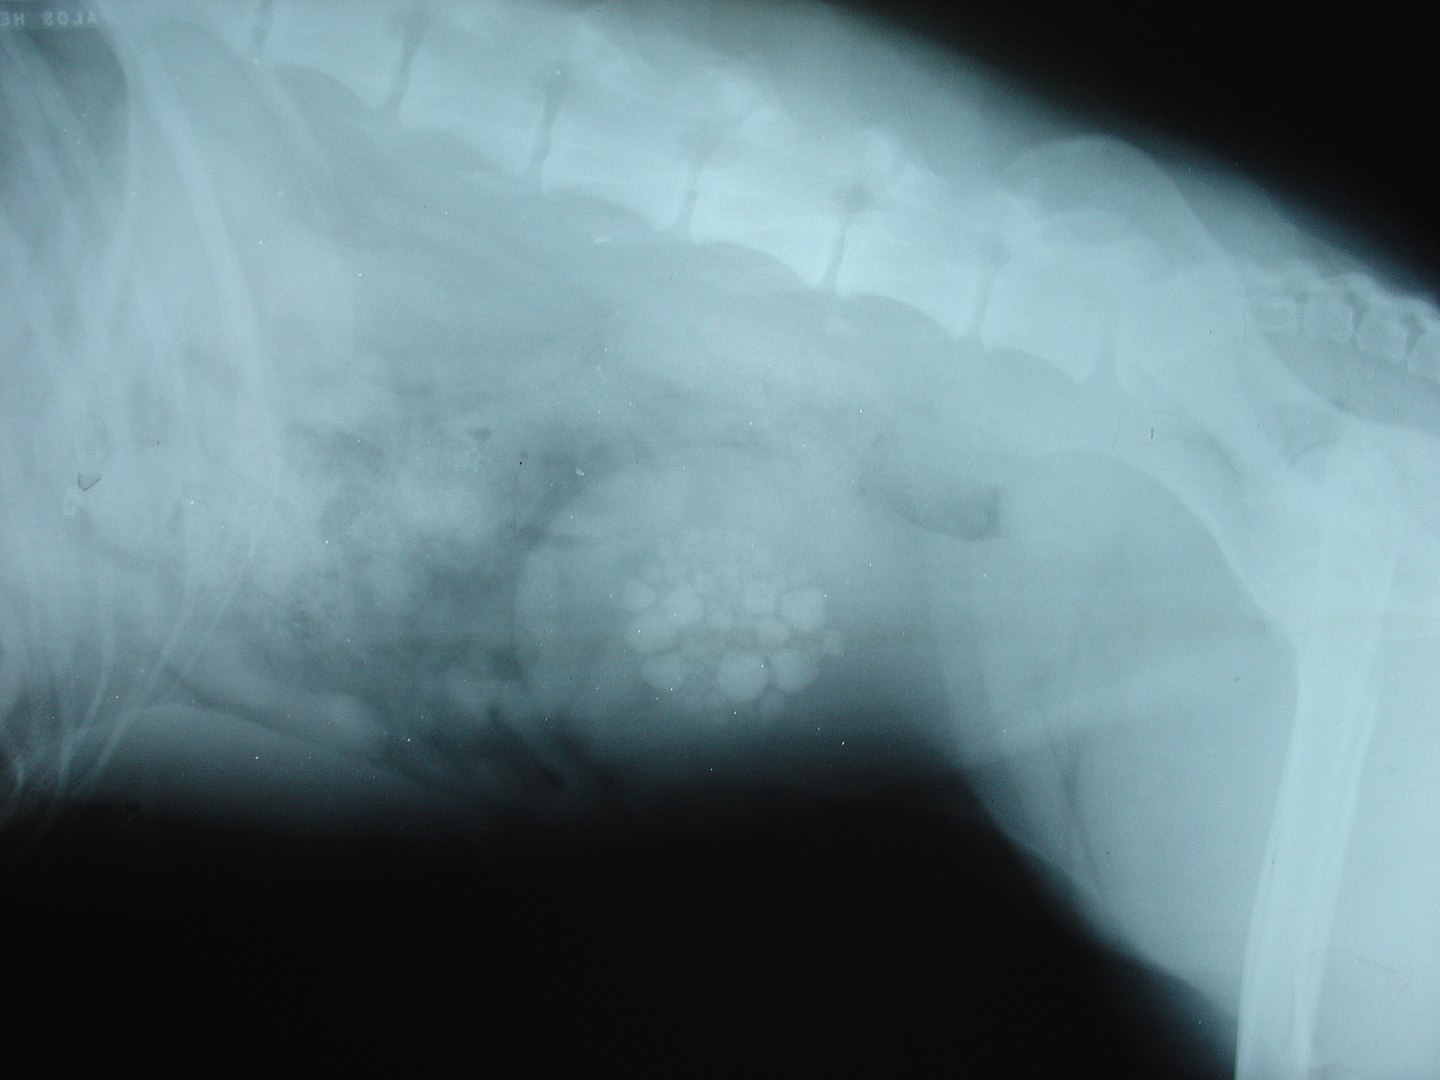

How to Prevent Bladder Stones in Dogs One Top Dog How To Prevent Bladder Stones Learn what causes them, what. When bladder stones are too large to pass naturally from. There is no surefire way to prevent bladder stones, and some people get them despite taking the best preventive measure. Learn how bladder stones are diagnosed and treated, and what factors can increase your risk of developing them. Learn how to prevent bladder. Can i. How To Prevent Bladder Stones.